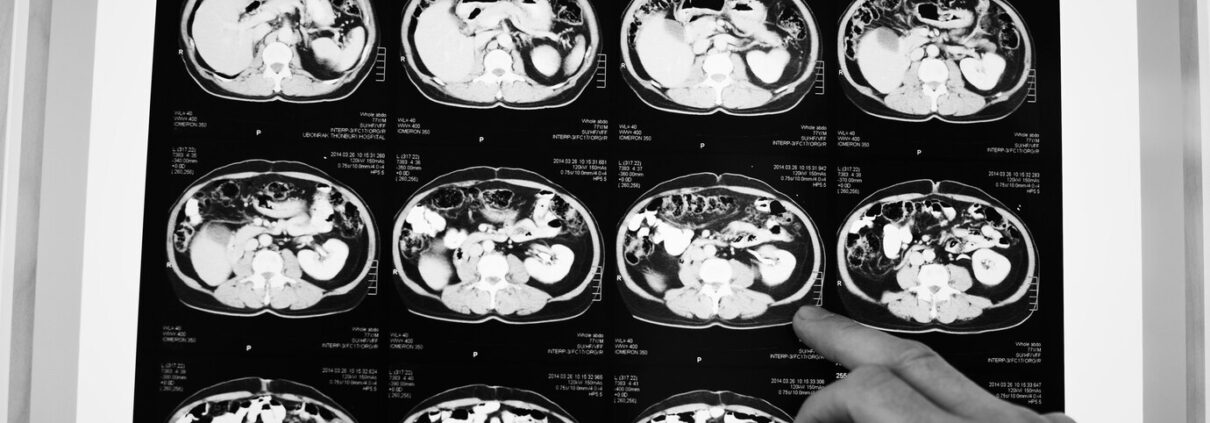

Brain tumours are identified using a CT or MRI scan. An expert who interprets scans (radiologist) will be able to see if you have an abnormality, which they may call a tumour.

MRI and CT scans

Below you will find information about MRI and CT scans, how they work and the differences between them:

CT scan – computerised tomography.

Instead of sending out a single x-ray through the body, several beams are sent simultaneously from different angles. The computer then processes the results showing them as a 2D picture. CT scans are less expensive and take less time than an MRI scan, but they have lower resolution so could potentially not show some skull base and low grade tumours, as well as an MRI scan. So, if you have one type of scan rather than another, it is usually because one will be more suited to you.

A CT scan usually lasts around 20 minutes and is quieter than an MRI scan. You lie on a table and the scanner moves around your head. If you need a contrast scan, then an iodine-based contrast agent will be injected. This shows the ‘leaky’ blood vessels in a tumour and enables the neuroradiologist to see the mass directly.